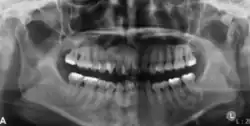

Panoramic radiograph showing a radiolucency around the distal root of the first mandibular molar[25]

Panoramic radiograph showing a mixed radiopaque-radiolucent lesion around the root of the left first mandibular molar [25]